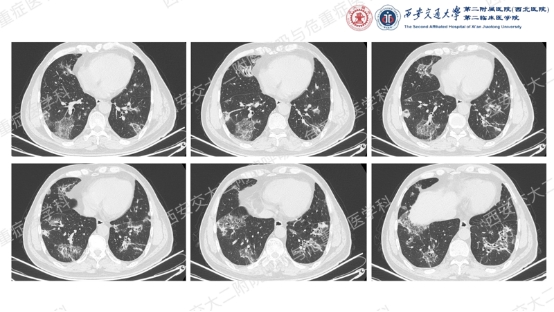

让我们一起从影像入手,看看这名患者的胸部CT特征:双肺多发斑片、实变和磨玻璃影,胸膜下和支气管血管束周围分布为主,病灶无明显空洞、钙化,可见散在支气管充气征,反晕征(中心磨玻璃影 + 外周环形实变影)尤为显著,伴典型“环礁征”(病灶边缘呈结节状隆起,类似环礁形态)。基于这些特征性影像学表现,同时排除细菌、真菌、结核感染及结缔组织病、肿瘤等常见病因,临床诊断隐源性机化性肺炎(COP)。

COP是一种病因不明的机化性肺炎(OP),属于特发性间质性肺炎的亚型,由肺部不明原因损伤引发的局部炎症及修复异常所致。其临床以急性或亚急性起病为特征,影像学表现具有“五多一少”的典型特点,是诊断及鉴别诊断的核心依据:

①多态性:可呈斑片状、实变状、团块状、条索状、地图状、结节状、粟粒状、网织状等各种形态,以前4种比例较高,每例患者多同时具有2种以上的形态。

②多发性:COP多为两肺多发性病灶。

③多变性:病灶有明显的游走性,具有此起彼伏的特点,多数病例在1周内可见观察到病灶的明显变化。抗感染治疗基本不影响病灶的变化。

④多复发性:文献报道的复发率多在13~58%之间。

⑤多双肺受累:两侧中下肺分布为主,占88%;沿着胸膜分布占96%,不累及胸膜占40%。

⑥蜂窝肺少见:仅有少数晚期重症COP出现蜂窝肺,发生率为4%。

本例患者虽未获得典型的病理确诊依据,但结合其“双肺多发胸膜下病灶、反晕征+环礁征”的特征性影像学表现、抗感染治疗无效的临床经过,以及全面排除感染、肿瘤、结缔组织病等其他病因,临床诊断COP的依据已充分。